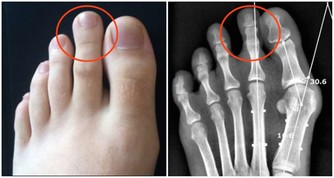

毛囊退化,無法製造黑色素,進而產生白髮

當毛囊內的黑色素細胞發生退化,就無法再製造黑色素,於是產生白髮。

一般醫學普遍認為,毛囊退化產生的白髮不可逆轉,但若是由於睡眠不足、壓力大、少運動等引起頭皮血液循環不佳,導致血液無法輸送到頭皮,使頭皮毛囊黑色素細胞無法正常分泌黑色素,而引起白髮,此類情形通常可藉由調整生活作息而改善。